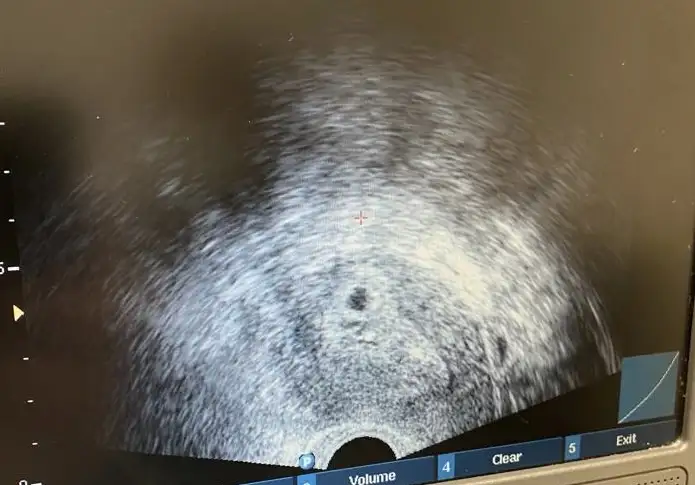

Vajinalden göründü

Vajinal mi gördü karından mıKızlaaar tünaydınnn, biz bugün 4+6’da keseyi gördük çok şükürbir problem yok dedi ama yolk ya da bebeği daha göremedik bayramdan sonra görürsünüz dedi.

Karından hiç bakmadan vajinal bakıcam dediVajinal mi gördü karından mı